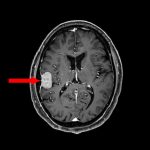

手術前1

手術前2